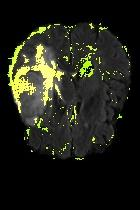

Current unsupervised anomaly localization approaches rely on generative models to learn the distribution of normal images, which is later used to identify potential anomalous regions derived from errors on the reconstructed images. However, a main limitation of nearly all prior literature is the need of employing anomalous images to set a class-specific threshold to locate the anomalies. This limits their usability in realistic scenarios, where only normal data is typically accessible. Despite this major drawback, only a handful of works have addressed this limitation, by integrating supervision on attention maps during training. In this work, we propose a novel formulation that does not require accessing images with abnormalities to define the threshold. Furthermore, and in contrast to very recent work, the proposed constraint is formulated in a more principled manner, leveraging well-known knowledge in constrained optimization. In particular, the equality constraint on the attention maps in prior work is replaced by an inequality constraint, which allows more flexibility. In addition, to address the limitations of penalty-based functions we employ an extension of the popular log-barrier methods to handle the constraint. Comprehensive experiments on the popular BRATS'19 dataset demonstrate that the proposed approach substantially outperforms relevant literature, establishing new state-of-the-art results for unsupervised lesion segmentation.

翻译:目前未受监督的异常本地化方法依靠基因模型来了解正常图像的分布,这些模型后来被用于确定从重建图像错误中得出的潜在异常区域。然而,几乎所有先前文献的主要局限性是,需要使用异常图像来设定一个特定等级的阈值以定位异常。这限制了其在现实情景中的可用性,在现实情景中,只有通常能获取正常数据。尽管存在这一重大缺陷,但只有少数作品通过在培训中整合对关注地图的监督,解决了这一局限性。在这项工作中,我们提议了一种新颖的提法,不要求使用异常图像来界定阈值。此外,与最近的工作相反,拟议的限制是以更加有原则的方式拟订的,在限制优化时利用众所周知的知识。特别是,先前工作中对关注地图的平等性制约被一种不平等性制约所取代,这允许更大的灵活性。此外,为了解决基于惩罚的功能的局限性,我们采用了流行的日志障碍方法来应对这一制约。我们建议对流行的BRATS'19数据设置进行综合实验,这与最近的工作不同,因此,拟议的限制是以更加有原则的方式提出了限制,即拟议的方法大大地超越了相关的分段结果。